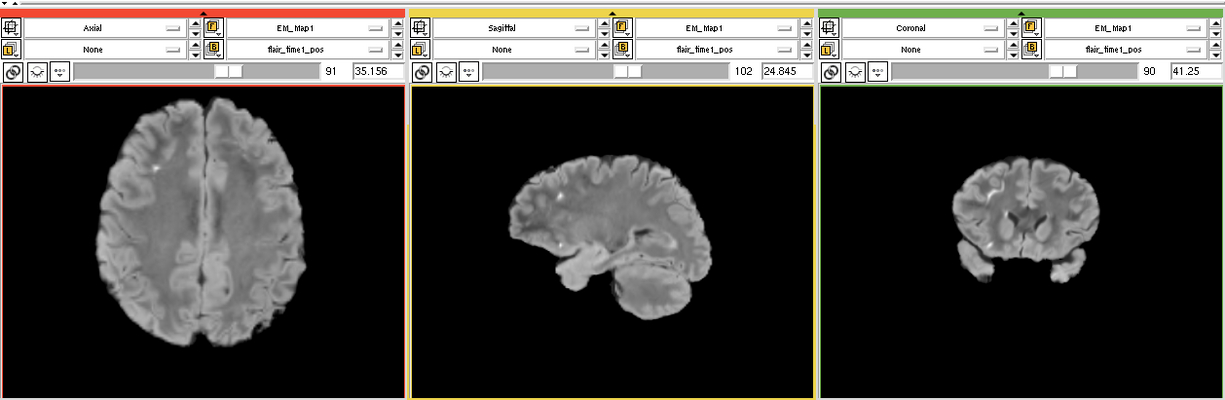

The goal is to segment white matter lesions based on T1 and FLAIR brain scans.

We want to use the EMSegmenter module for this project. The plan is to create a two channel pipeline which includes pre-processing (e.g. registration) and applying the EM algorithm to perform the segmentation.

We created a 2 channnel(T1+FLAIR) pipeline for this project. Intensity values of the lesions are calculated automatic but have to manually updated to get a better result. (see segmentation screenshot)

Open: With this approach we detect a lot of false positives outside the white matter region.